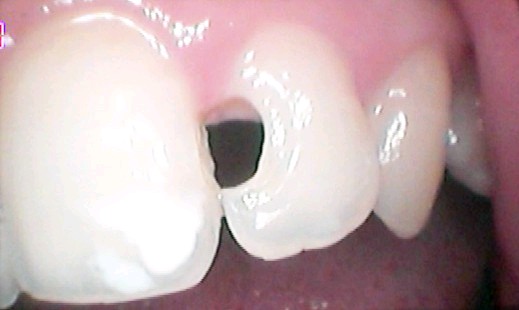

如果像下(图六)龋坏面积大就不建议做补牙了,需选择全瓷贴面修复。

图六

(图七)箭头所指的位置两年因大面积龋坏做充填术,先补牙材料颜色发黄,补牙材料与牙齿之间出血裂痕。右图是拆除原补牙材料改做全瓷贴面修复。

图七